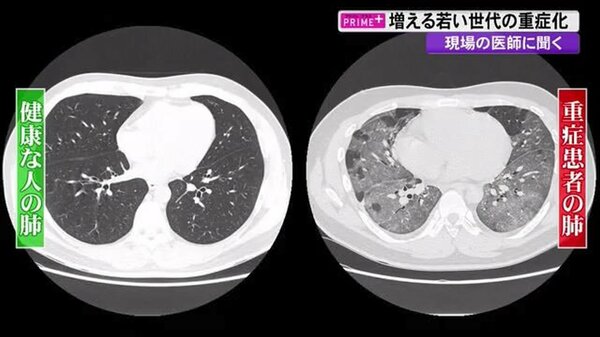

ウイルスの急速な変異に遅れないようにするのは容易ではない。専門家の見解は、これまでの変異のほとんどが、ウイルスが宿主に与えるダメージの大きさではなく、ウイルスが広がる効率の良さに関連したものであるという点で一致している。2021年7月に発表された研究では、デルタ株はそれ以前の株に比べて、ヒトの肺や咽喉の中で、より速く、より高いレベルで増殖すると報告されている26。